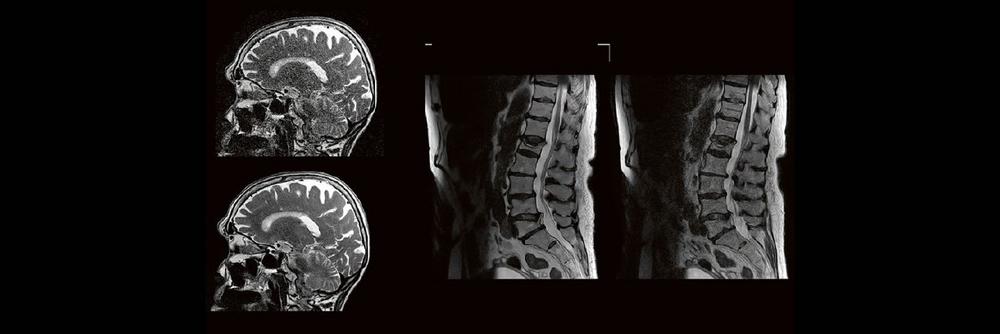

Professor Dr. med. Marc Brockmann WEITERENTWICKLUNGEN VON KOPF BIS FUSS BEIM VC Oberstarzt Dr. med. Stephan Waldeck DEEP-LEARNING-REKONSTRUKTION IN DER NEURORADIOLOGIE Die CT ist ein essentielles Routine-Verfahren in der Neuroradiologie. Bei steigender Bildqualität konnte die Röntgendosis mit neuen Technologien in der letzten Dekade deutlich gesenkt werden, was für die zielgerichtete und möglichst schonende Behandlung von